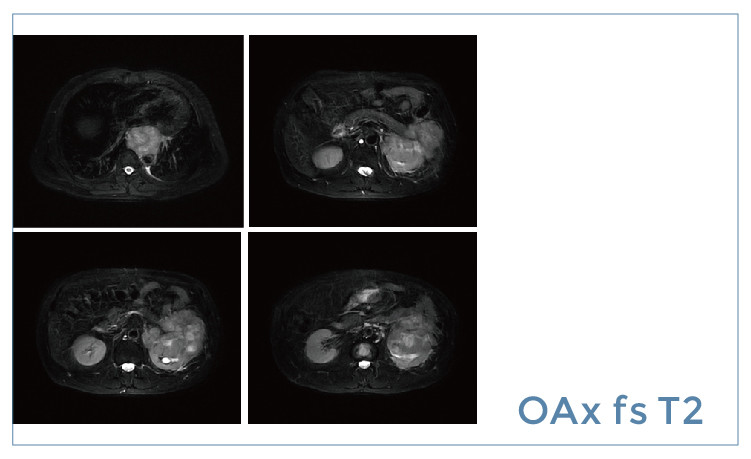

【朗润影像档案】20190524磁共振影像病例结果讨论

【朗润影像档案】磁共振影像病例分享(编号20190524)